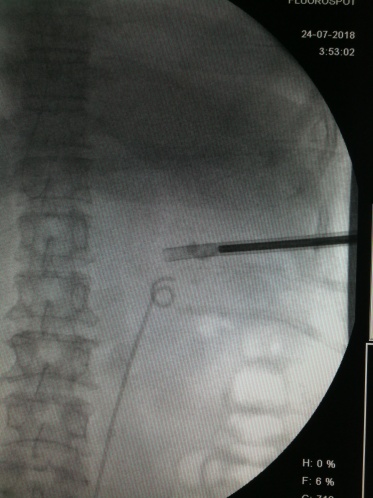

1、术前点片,确定结石位置

X线定位下穿刺 碎石

在充足的术前准备后,李逊教授团队为林阿姨施行“微创右侧经皮肾镜取石术”。此次手术单通道取了一大半结石,将肾盂打通,留置双J管。根据术后复查结果,林阿姨体内还有三个平行的狭长肾盏结石存在,通过再次取石治的疗,经验丰富的医疗团队终于为林阿姨取尽结石。

据医生术后计算,整个手术在X光机下曝光203次,可谓是在“光合作用”下完成了整个手术操作。另外,该手术有些结石角度大,主刀无法启动碎石器,由主刀固定手术视野,助手启动碎石器,四个医生完美配合下完成了整台手术。